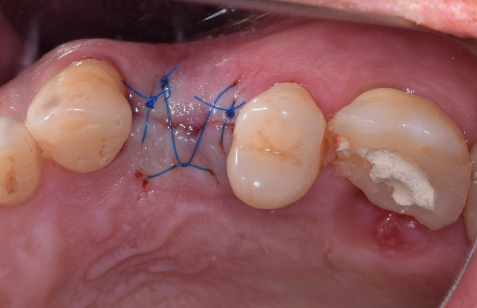

După perioada de osteointegrare a implantului acesta se descoperă, adică se creează o cale de comunicare cu mediul bucal, el până în această etapă fiind acoperit de gingie. Se instalează apoi un bont de vindecare care are rolul să ghideze vindecarea gingiei în jurul implantului.(Fig. 3.5.5 și 3.5.6) Cu acest bont pacientul așteaptă o perioadă variabilă de 14-21 de zile, iar dacă după acest interval gingia este vindecată, se poate trece la etapa următoare – cea de amprentare.